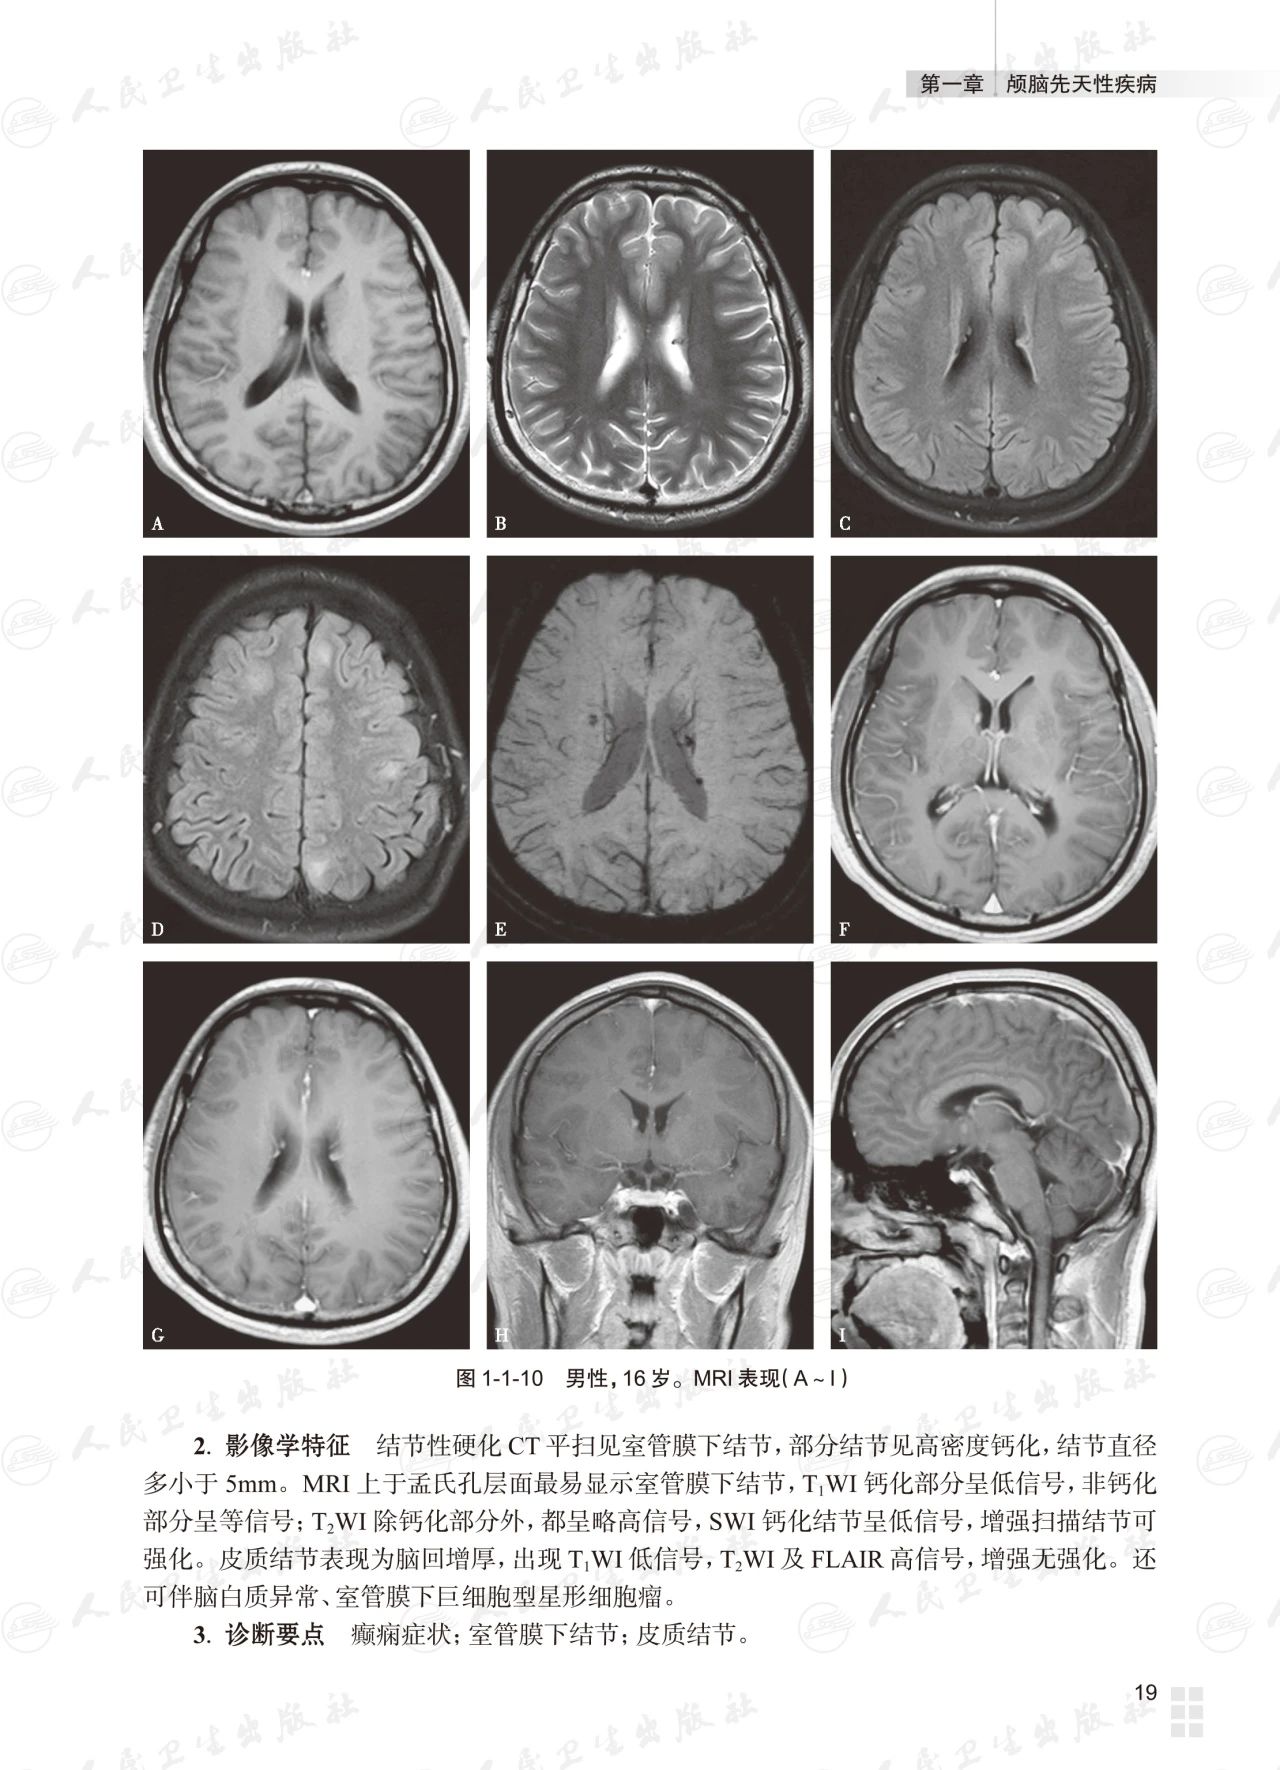

基础篇为常见颅脑疾病多模态磁共振成像典型病例分析,以复习为主,从疾病的临床与病理入手,解析影像学特征,提供影像诊断思路,最终给出诊断要点;